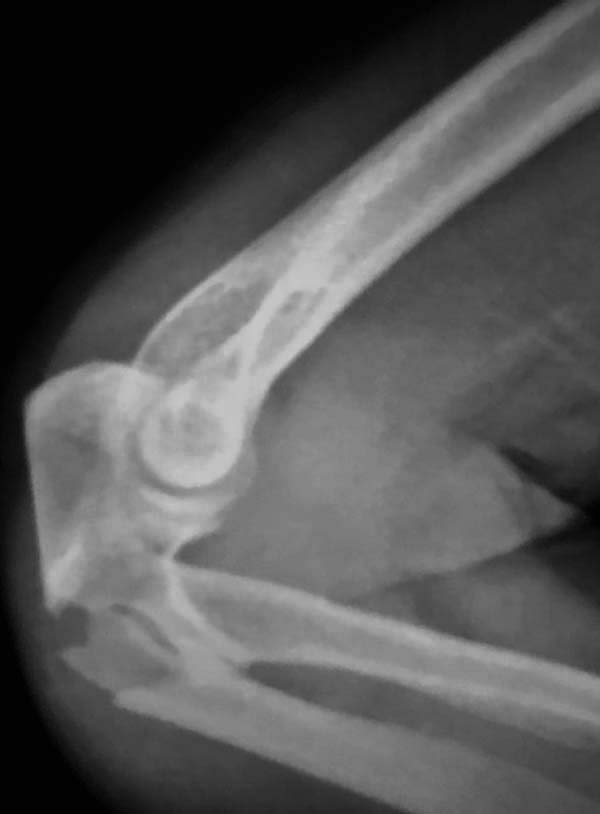

Добрый день, коллеги. Какие мнения будут по этому снимку?

А так, здесь имеется многофрагментарный проксимальный перелом локтевого отростка с переломо-вывихом головки лучевой кости по классификации Mason III. Решение принимается на основании КТ срезов, потому что на боковом рентген снимке вроде отсутствует смещение, где сустав и контур Coronoid в одном блоке, а на прямом подозрение на смещение в Coronoid?

Для перелома локтевого отростка придуманы много пластин, надо выбрать по длине. А при краевых переломах головки ее окружность можно восстановить винтами 2 мм, но в данном случае имеется полный вывих головки и фиксация, даже специальной пластиной, может осложнится. Протез головки после удаления предупреждает нестабильность в суставе и деформацию оси конечности в будущем!

Конверсионные спицы на уровне проксимального отдела лучевой кости интересная идея, но на уровне перелома в области шейки трудно удержать головку. Предварительная репозиция локтевого отростка с временной установкой пластины, затем удаление экономит время. Доступ через локтевой отросток, где можно фиксировать или удалить головку с замещением, а потом установить пластину обратно на локтевой отросток!